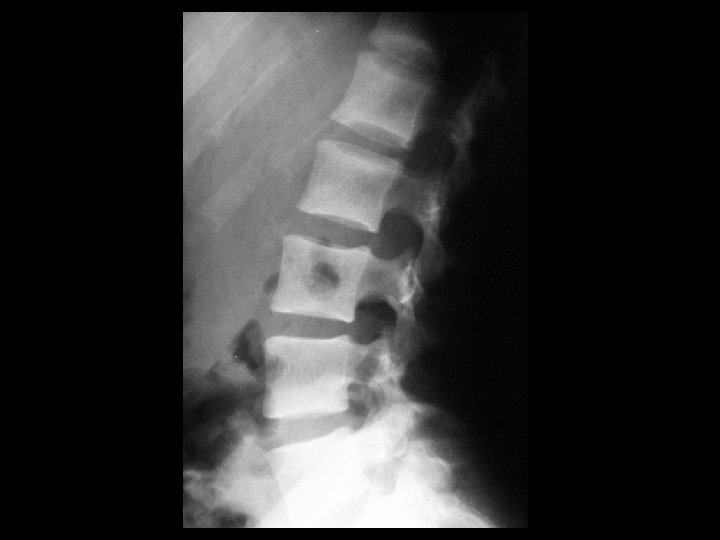

Discitis/Osteomyelitis • Findings: – L 4 -5 disc space and adjacent endplate sclerosis and destruction – ~50% anterolisthesis and gibbus deformity • ddx: – NONE! – This is an Aunt Minnie!